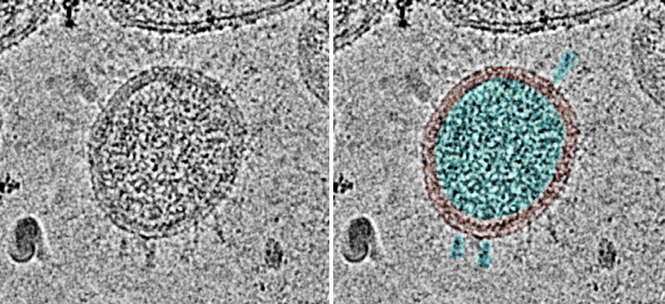

Punto 1: La figura 1 muestra micrografías electrónicas de tres virus diferentes cultivados en cultivos celulares similares. El lector puede juzgar por sí mismo si estos tres virus tienen el mismo aspecto o no. Punto 2: Se recomienda al lector que practique la búsqueda de enfermedades con causas aún desconocidas. Las inflamaciones del sistema nervioso central son un campo fructífero para ello. El fracaso de innumerables intentos de identificar los virus causantes de tales enfermedades demuestra, por supuesto, que los virólogos son muy capaces de distinguir las partículas de virus de los exosomas u otros componentes celulares. Esto significa que la hipótesis de los escépticos de los virus puede considerarse claramente falseada.

En el estudio de Liu et al [17], el virus se aisló de un único paciente. La secuencia sólo se determinó directamente a partir del material de muestra. El virus se cultivó en células y su identidad se verificó mediante PCR. Tras su propagación en cultivo celular, se inactivó mediante tratamiento químico, se purificó mediante varios pasos de centrifugación y finalmente se analizó mediante criomicroscopía electrónica. La forma de las partículas víricas observadas es típica de la familia de los coronavirus (Figura 3).

Figura 3: Micrografía crioelectrónica de una partícula de SARS-CoV-2. Toda la superficie está decorada con moléculas de proteína de espiga en su mayor parte borrosas. A la derecha, se han resaltado en color la nucleocápside interior, la membrana circundante y tres moléculas individuales de proteína espiga.